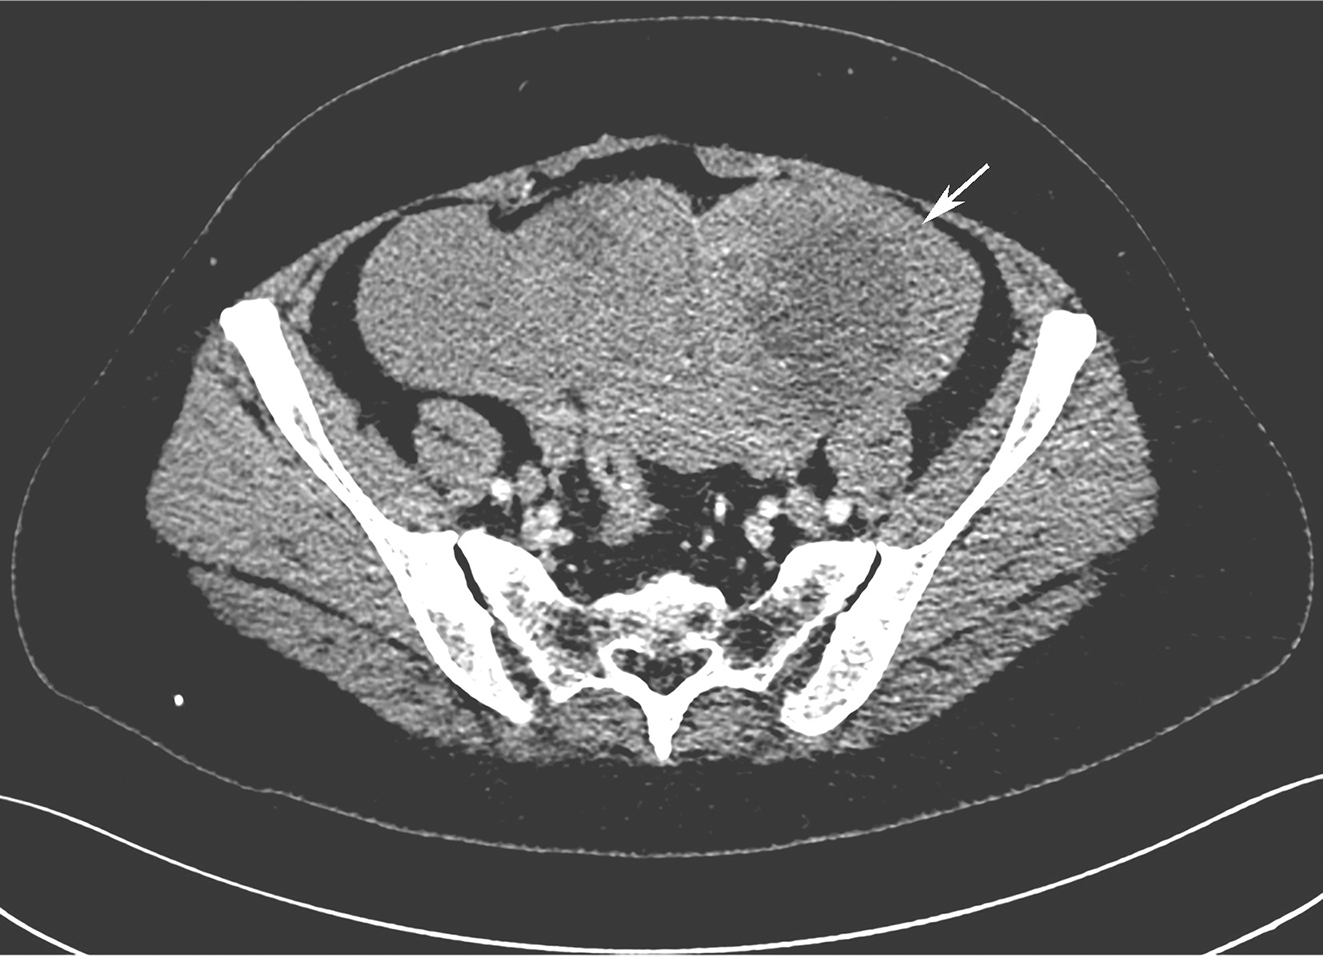

全腹增强CT:①盆腔积液、积血,盆腔软组织密度肿块影,最大截面约15cm×9cm,与子宫分界不清,增强扫描呈明显不均匀强化,内见血管影(图1);②左肾中上份见巨大不规则占位,最大截面约15cm×10cm,内散在点状钙化灶,增强扫描呈明显不均匀强化,左右肾受压下移(图2)。

图1增强CT示盆腔巨大占位

患者开始400mg/d伊马替尼治疗2周后,复查腹部CT见:①左肾中上份见巨大不规则肿块影,最大截面约15cm×10cm,其内密度不均匀,内散在点状钙化灶,增强扫描呈明显不均匀强化,可见粗大引流静脉,肾盂受压积液。肿瘤体积与前无明显变化。②盆腔偏右份见不规则肿块影,最大截面约9cm×9cm,增强扫描呈明显不均匀强化,盆腔肿块较前明显缩小(图3)。再次MDT讨论决定行同期肾脏肿瘤及盆腔肿瘤切除。

图3术前治疗后复查CT示盆腔GIST明显缩小